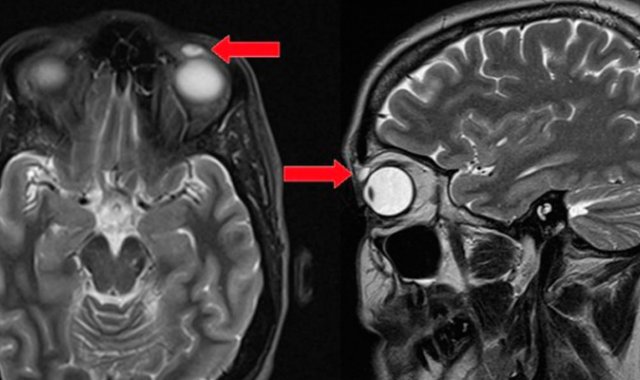

Perdió lente de contacto y, 28 años después, lo encontró en su ojo

Un golpe producido durante un juego de bádminton, fue el responsable de mover el lente hasta el párpado.